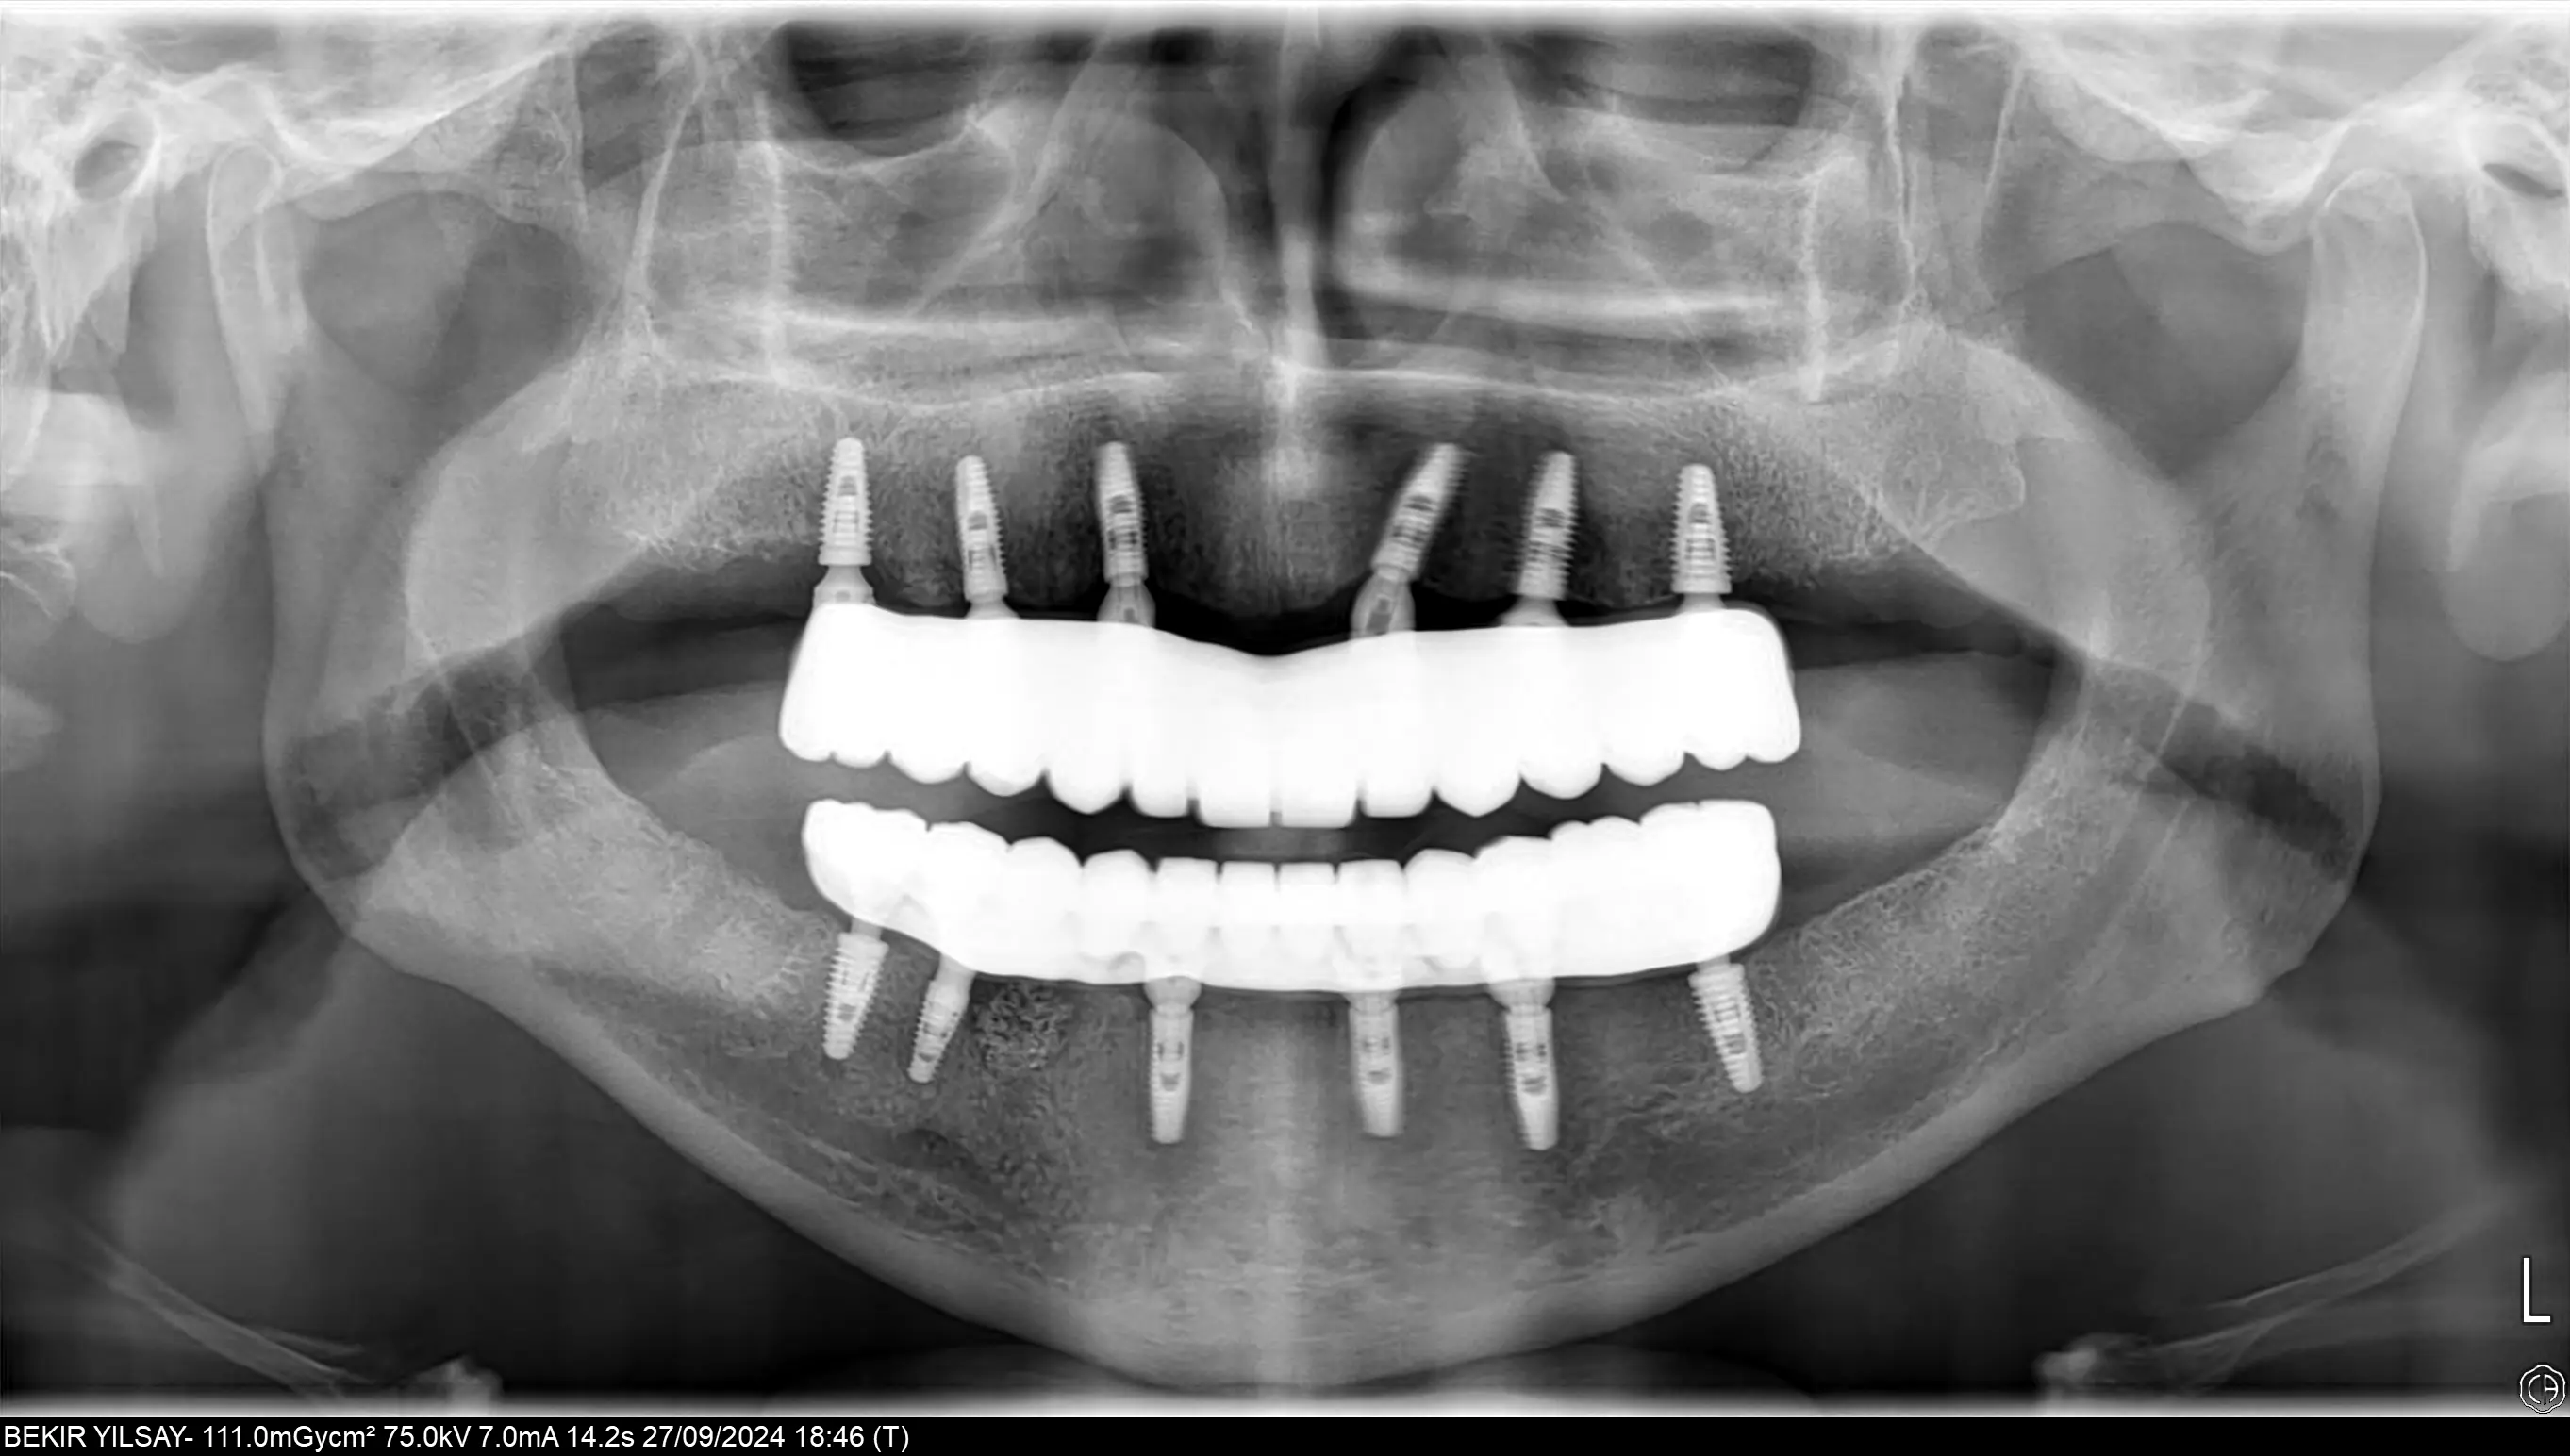

Tooth loss affects more than just your ability to chew; it can impact your speech, self-confidence, and overall facial appearance. All-on-6 dental implants offer a modern, full-arch restoration for patients with multiple missing teeth, providing a stable, comfortable, and permanent solution. In this technique, six biocompatible titanium implants are strategically placed in the jawbone to support full-arch prosthetic teeth. These implants act as a powerful anchor, creating a secure foundation for your new smile.

Unlike traditional removable dentures, All-on-6 implants are fixed, meaning they do not slip or shift. They offer the feel and function of natural teeth, allowing you to eat, speak, and smile with confidence. Additionally, implants help preserve jawbone density, preventing bone loss and maintaining facial structure over time. With their natural aesthetics, long-lasting durability, and high patient satisfaction, All-on-6 implants are a transformative solution to restore both the function and beauty of your smile.

At Attelia, our All-on-6 restorations are supported by a titanium frame that provides superior durability and ensures chewing forces are distributed equally across all six implants. This enhances patient comfort and guarantees long-term success. To increase precision and functionality, we use multi-unit abutments on each implant, ensuring optimum angles, alignment, and a more natural bite.

All-on-6 provides better stability, stronger biting force, and more even load distribution by using six implants per jaw instead of four. The use of multi-unit abutments and titanium frameworks further improves alignment and long-term success, making All-on-6 ideal for patients seeking maximum support and durability.